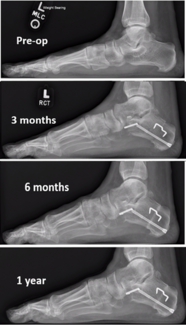

Nathan Ptak, DPM; Brady Mallory, DPM, FACFAS

In the case study presented, progressive correction and stability of the first ray was obtained without the addition of a Cotton osteotomy, in the presence of a flexible forefoot varus with a dorsiflexed first ray intraoperatively. This case...